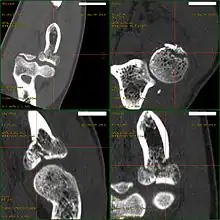

Radial head fractures are diagnosed from an assessment and diagnostic imaging. Assessment may include pain or tenderness at the radial head, bruising, swelling, and a limited range of motion of the elbow.[7] Diagnostic imaging may include ultrasound, plain X-ray, CT scan, and magnetic resonance imaging (MRI).[7][8] A fat pad sign may be present on diagnostic imaging and may indicate a radial head fracture.[9]

CT scan demonstrating the Mason type III radial head fracture

CT scan showing a radial head fracture